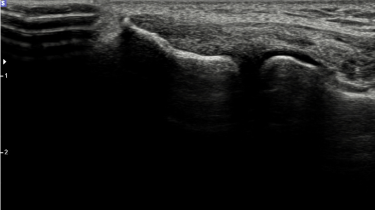

2022.10.18

테니스엘보 치료 전 MRI

2023.02.17

테니스엘보 치료 후 MRI